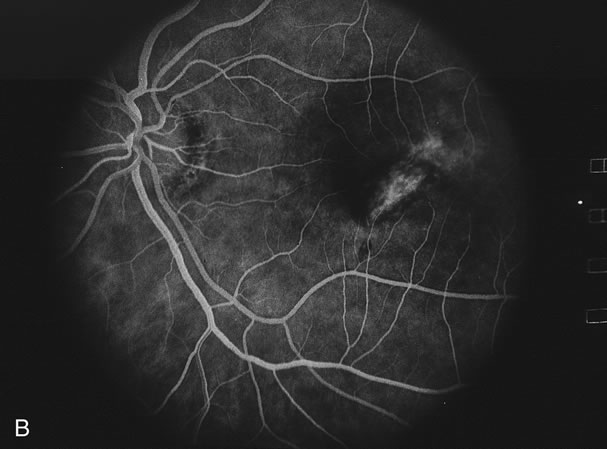

The classic findings in the acute cases are lesions of variable size that are hypofluorescent in the early phase of the fluorescein angiogram. In the late phases of the angiogram there is hyperfluorescence of the lesions. In the late phases, there also may be leakage from the disc as well, and there also may be staining of the retinal vessels because of the vasculitis. With resolution of the disease, there still may be a mottled pattern of fluorescence correlating with the areas of pigment clumping and pigment atrophy (Fig. 8).

Fig. 8. A. Early fundus angiogram showing hypofluorescence of the acute posterior multifocal placoid pigment epitheliopathy (APMPPE) lesions. B. Later stage of the angiogram showing staining of the APMPPE lesions.